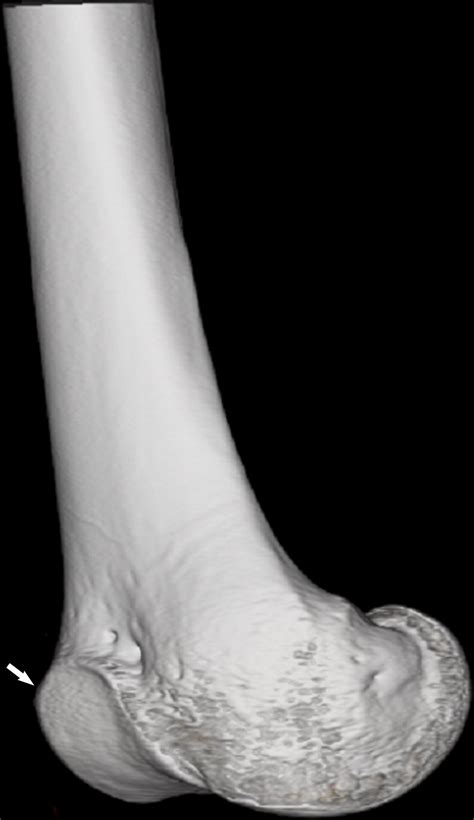

Diagnosing patella tracking problems typically involves a combination of a physical examination and imaging tests. A healthcare provider will assess the knee's range of motion, strength, and alignment, and may perform specific tests to evaluate patellar tracking. Imaging studies, such as X-rays, MRI, or CT scans, can provide detailed views of the knee joint and help identify any underlying structural issues.

• Anatomical Abnormalities: Structural issues such as a shallow trochlear groove, a high-riding patella, or a misaligned tibial tuberosity can disrupt the patella's movement.